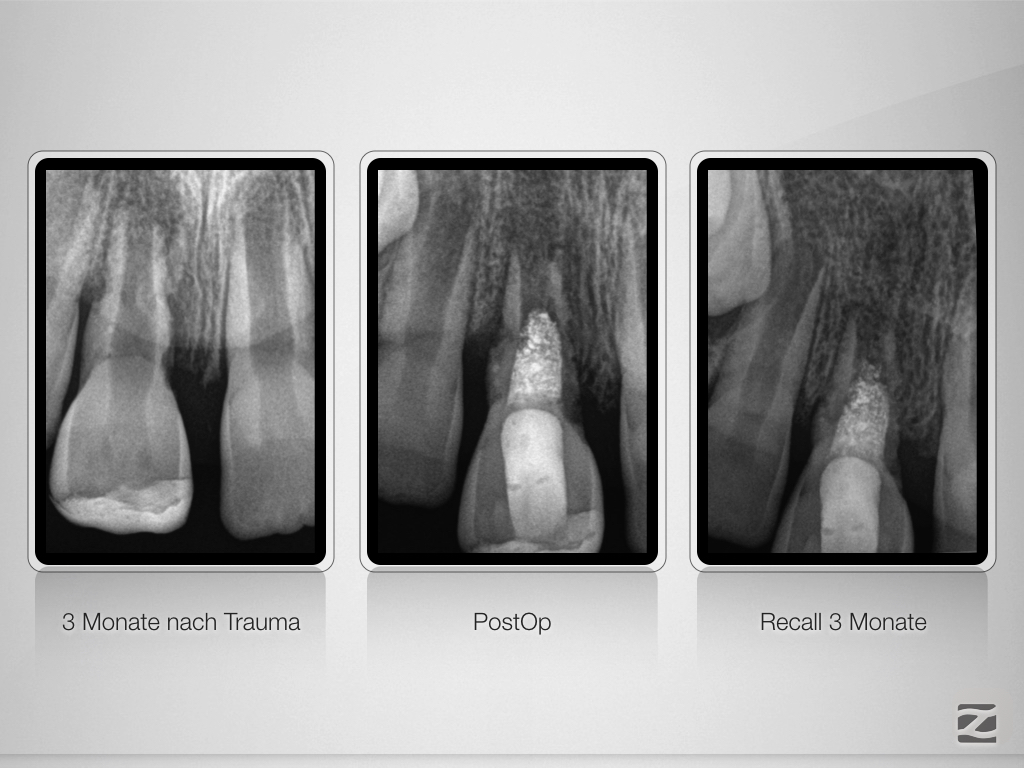

Bestmöglicher Kompromiss